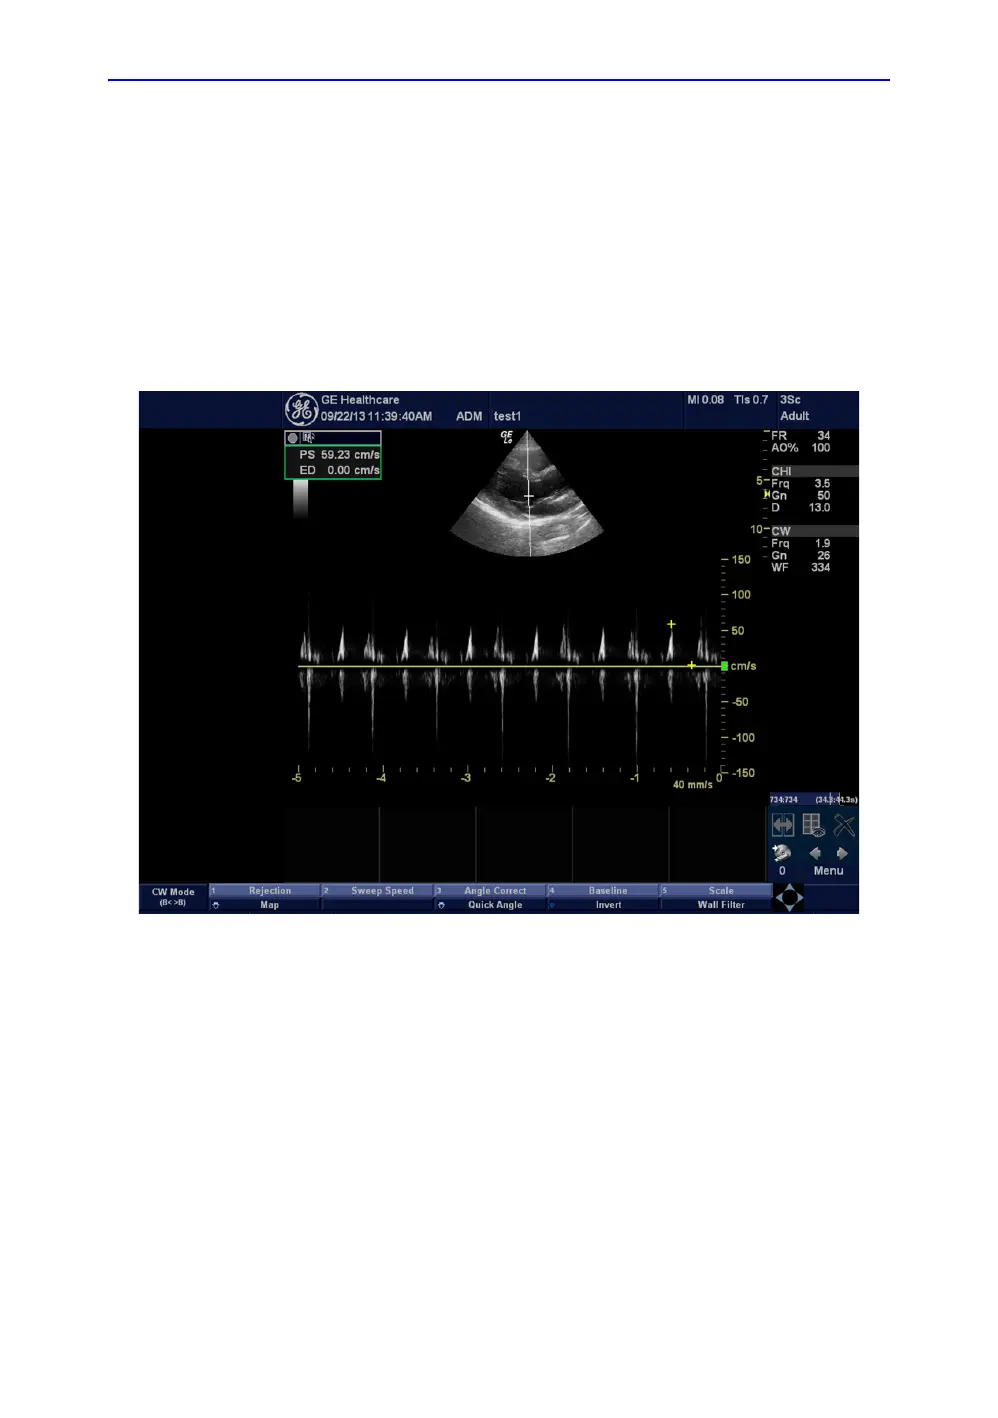

CWD Functional Check

CW Doppler are used to measure velocity (most often in blood).

Doppler mode can be done with a special pencil probe or with

an ordinary probe. By using an ordinary probe, you can first

bring up a B Mode picture for navigation purpose and then add

CW Doppler.

CWD Mode Screen Example

Figure 4-19. CWD Mode Image Example